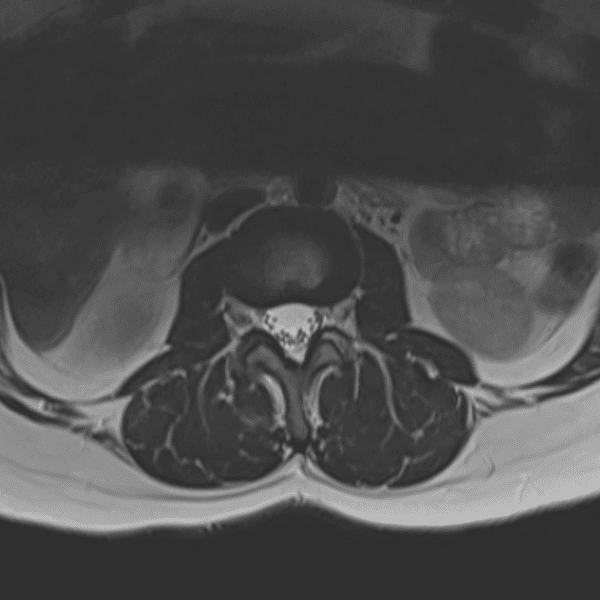

Simulates call by including subtle or difficult cases and some normals.

35 cases